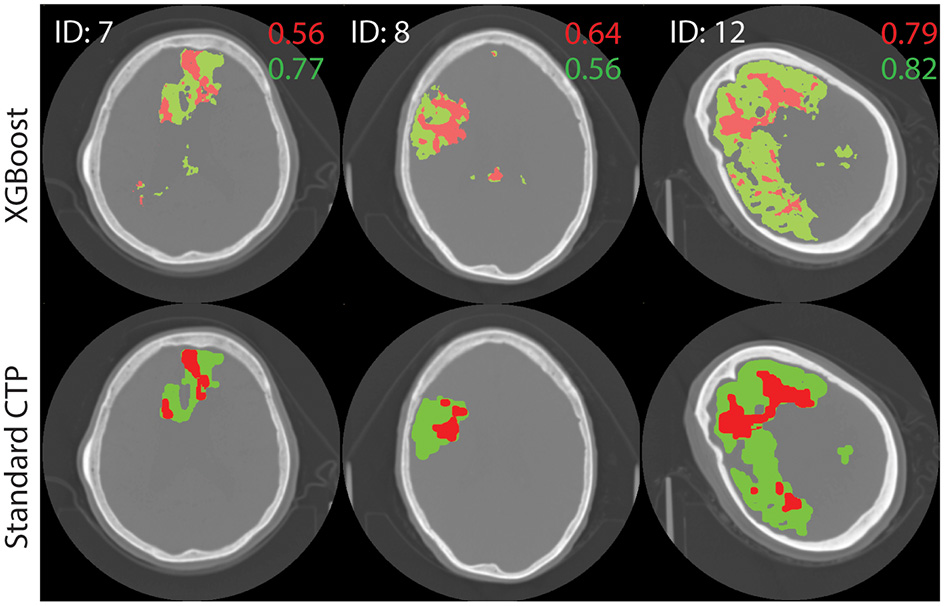

The performance of the best performing model (shown in bold in Table 3) was tested on the remaining 22 images in the test set. The results are shown in Supplementary Table A1. Figure 4 shows axial slices of lesion predictions (overlayed on non-contrast CT image slices) using the model based on all four CTP maps for a selection of datasets (subjects 7, 8, and 1 with reference to Supplementary Table A1).

Figure 4

Test image results. A single axial slice, selected to clearly display the lesion, is shown from each image. The results of processing test images through the XGBoost model to make a prediction on the class label is shown at top. Standard lesion maps are shown at bottom. The predictions for core (red) and penumbra (green) are shown on top of a single axial slice of the brain, obtain with non-contrast CT. Dice similarity score are shown on the image, in corresponding colors.

For all 22 patients, the mean DSC values for core and penumbra were 0.39 (SD 0.26) and 0.50 (SD 0.22), respectively, and the mean JI values for core and penumbra were 0.28 (SD 0.23) and 0.36 (SD 0.20), respectively. For both core and penumbra, JI and DSC were significantly different across the dataset (core: paired t-test, p < 0.0001; penumbra: paired t-test, p < 0.0001).

For the testing images, DSC and JI scores were shown to vary significantly even though they are both commonly used similarity metrics. In addition, both metrics varied significantly with volume. Therefore, the DSC or JI score for a large lesion may not represent the same accuracy as for a small lesion, even though (27) has proposed otherwise (35, 36). For example, the large core in Figure 4 (ID = 12, M1) receives an almost perfect DSC value, while the smaller cores received lower DSC scores; these differences may have resulted merely from size differences. The same behavior was seen with JI. An average DSC or JI score that is a result of the summing over results from lesions of different sizes will not be an accurate representation of the overall performance of a model. We propose a weighted mean DSC/JI to account for size variation before these scores can be fully interpretable. Further studies will explore the application of a weighted mean. In lieu of a robust and subjective model performance metric, benchmark data [ISLES 2018 (37)] will be used in future studies to report performance.